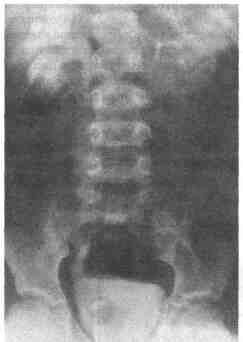

1. Что такое уретероцеле? Уретероцеле — это кистозное расширение дистального конца мочеточника в интраве-зикальном сегменте (рис. 41-1.). 2. При каком строении мочевыводящих путей развивается уретероцеле? Несмотря на то, что уретероцеле может развиться

Рис. 41 -1. Внутривенная урограмма, на которой определяется простое ортотопическое уретероцеле 3. Почему развивается уретероцеле? В настоящее время существует три теории развития уретероцеле: • обструкция устья мочеточника; • неправильное мышечное строение дистального отдела мочеточника; • чрезмерная дилатация дистального мочеточника в ходе развития. 4. Зависит ли от пола частота встречаемости уретероцеле? Нет. Уретероцеле в одинарных системах развивается преимущественно у мальчиков и редко наблюдается у девочек. Наоборот, эктопические уретероцеле, те, что выявляются при удвоении систем, чаще определяются у девочек. 5. Каковы проявления уретероцеле? В настоящее время уретероцеле чаще всего диагностируют при ультразвуковом исследовании почек. При ультрасонографии плода устанавливают диагноз гидронефроза. Он может быть обусловлен наличием уретероцеле, которое выявляют в ходе обследования в послеродовом периоде. Уретероцеле можно также увидеть при физикальном обследовании. Эктопическое уретероцеле может пролабировать через мочеиспускательный канал и представлять собой объемное образование, расположенное между половыми губами. Оно также может выходить из мочеиспускательного канала и появляться между половыми губами в виде кистозного объемного образования. До внедрения ультразвукового исследования инфекции мочевыводящих путей были наиболее часто встречающимся первичным проявлением заболевания. У многих детей до сих пор заболевание начинается с появления этих симптомов. 6. Как лучше всего диагностировать уретероцеле при ультразвуковом исследовании? 1 Ультрасонография является лучшим первичным этапом диагностики уретероцеле Ультразвуковое исследование назначают в качестве контрольного обследования для оценки внутриутробного развития плода или при диагностике инфекции мочевыводящих путей Эта методика позволяет визуализировать верхние мочевыво-дящие пути и выявить гидронефроз Она также позволяет обнаружить кистозное объемное образование в нижней части дистального отдела мочеточника и в проекции мочевого пузыря 2 Подозрение на наличие уретероцеле при ультразвуковом исследовании может быть подтверждено при проведении микционной цистоуретерографии 3 Необходимо также провести сканирование